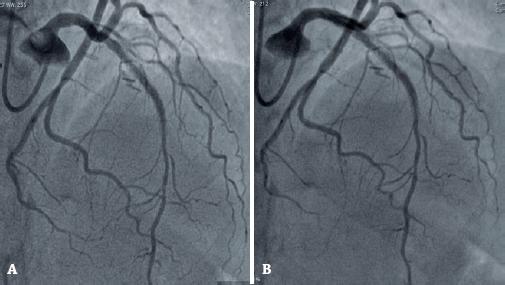

Figure 3

Hemodynamic study (2020). (A) Evidence of a patent stent in the left anterior descending artery. (B) Evidence of a patent stent in the left anterior descending artery.